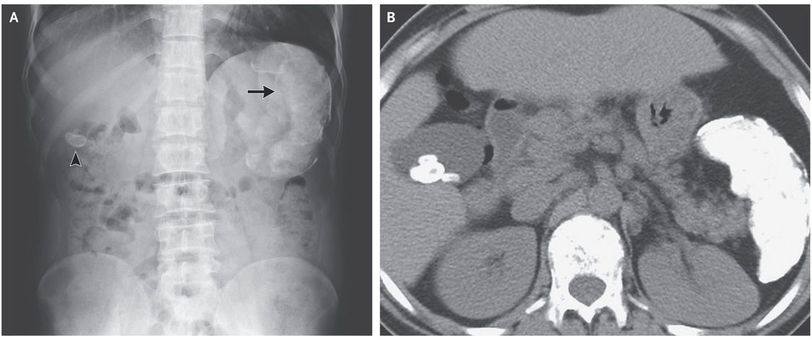

A 35-year-old man presented to the gastroenterology clinic for treatment of chronic hepatitis C virus (HCV) infection. He had a type of sickle cell disease, hemoglobin Sβ thalassemia, with recurrent, episodic abdominal pain that had been present since childhood. A complete blood count showed microcytic anemia. The total bilirubin level was 8.5 mg per deciliter (145 μmol per liter; reference range, 0.3 to 1.2 mg per deciliter [5.1 to 20.5 μmol per liter]) and the indirect bilirubin level was 6.2 mg per deciliter (106 μmol per liter; reference range, 0.1 to 1.0 mg per deciliter [1.7 to 17.1 μmol per liter]). A peripheral-blood smear showed microcytic and hypochromic red cells, target cells, nucleated red cells, and sickle cells. An abdominal radiograph, which was obtained during a previous presentation for abdominal pain, showed a radiopaque gallstone (Panel A, arrowhead) and a calcified spleen (Panel A, arrow). A computed tomographic scan of the abdomen, obtained without the administration of contrast material, showed multiple gallstones and a calcified splenic pulp and capsule (Panel B). Pigment gallstones may occur as a result of hemolysis. Bilirubin stones, which are normally radiolucent, can be radiopaque when bilirubin binds with calcium. This patient completed treatment for chronic HCV infection, and he was vaccinated against encapsulated organisms. He has continued to do well on follow-up visits. Ankur Gupta, D.M. Priyanka Jain, M.D. Max Super Specialty Hospital, Dehradun, India source: nejm.org